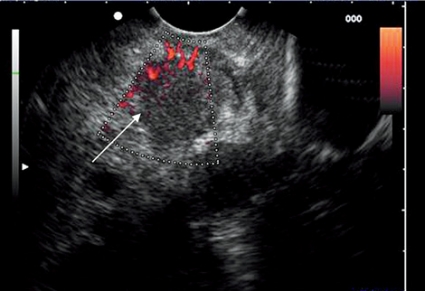

Neuroendokrina tumörer är ovanliga och namnges utifrån typ av peptid som tumören utsöndrar. De kan vara funktionella eller icke-funktionella, och den enda kurativa behandlingen är kirurgi, vilket gör att preoperativ lokalisering är kritisk. Tumörlokalisering med konventionella bildtekniker är ofta svår, men endoskopiskt ultraljud kan med hög tillförlitlighet detektera tumörer så små som 4–5 mm (Figur 9). Prospektiva studier har visat att endoskopiskt ultraljud kan lokalisera mellan 82 och 93 procent av alla neuroendokrina tumörer i pankreas. Andra studier har visat att endoskopiskt ultraljud kan identifiera neuroendokrina tumörer i pankreas bättre än somatostatinreceptorskintigrafi (oktreotidskintigrafi), DT och MR.

Vid behov av primär diagnostik och planering av behandling är det möjligt att genomföra EUS-FNA även på mycket små (4–5 mm) neuroendokrina tumörer.